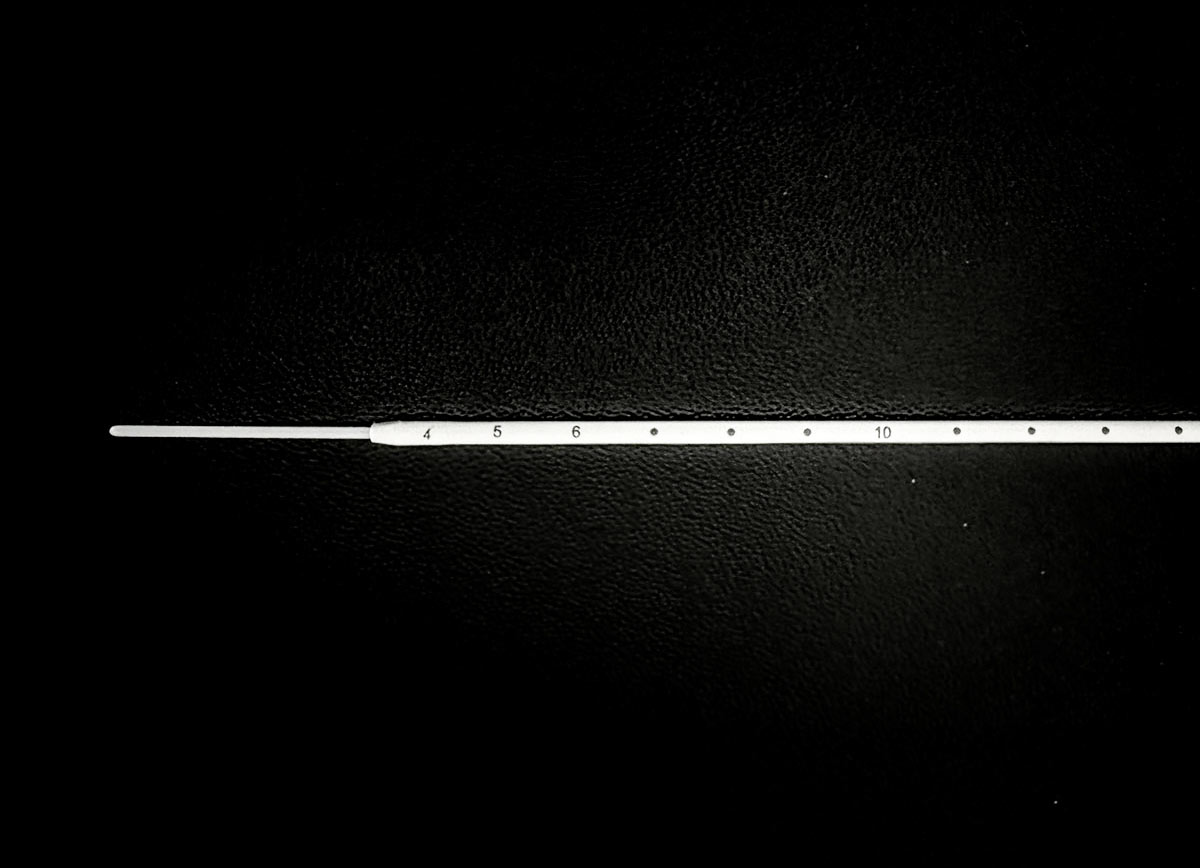

CONFIGURABLE TIP

Multiple porous tip designs: 1/2 cm, 1 cm, 2 cm, 3 cm, 4 cm, and 5 cm.